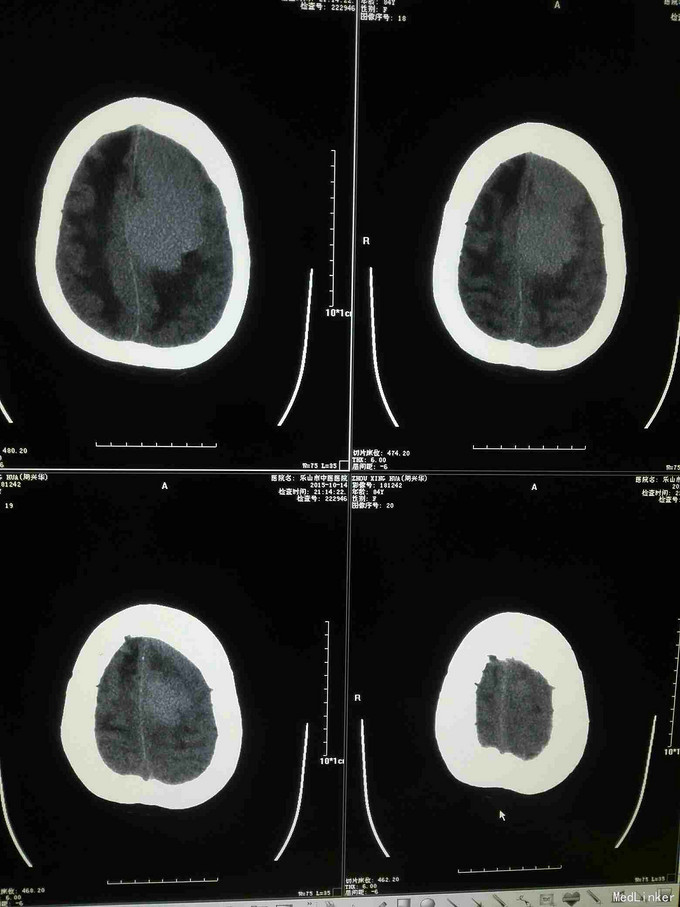

急诊CT病例

主诉 病史

昏迷不醒就诊